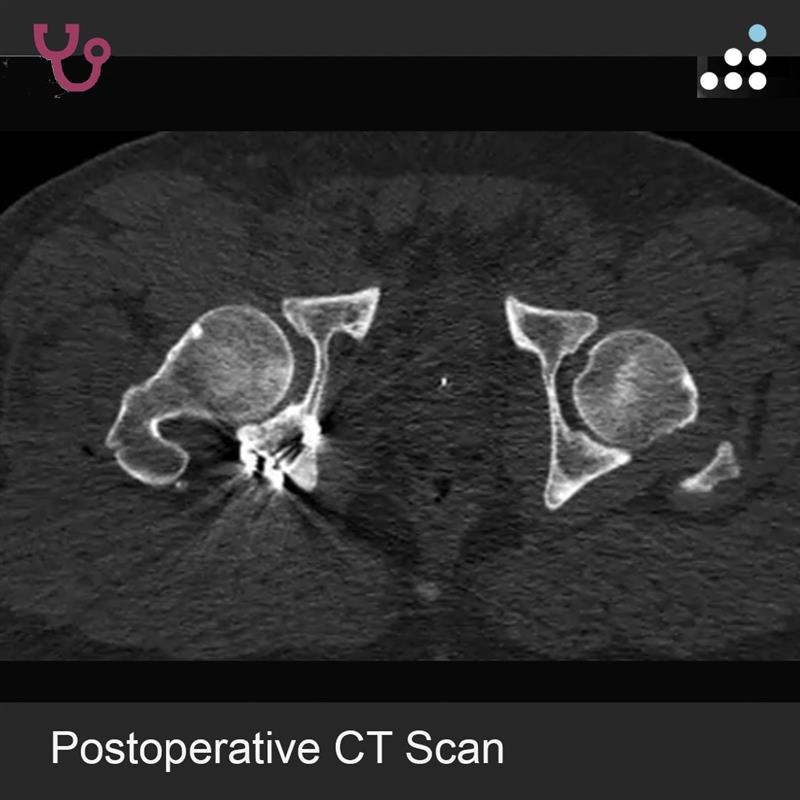

Can you answer our free question of the day? A patient presents to the trauma bay after involvement in a motor vehicle collision. Radiographs obtained in the trauma bay demonstrate a right distal femur fracture, as seen in Figure A. In surgery, the articular block is reduced, and reduction is held with headless compression screws. A retrograde intramedullary nail is then placed. After nail advancement, a varus and recurvatum deformity is noted at the fracture site with intraoperative fluoroscopy, as demonstrated via illustrations in Figures B and C. Placement of blocking screws in which locations (A - H) from Figure B and C would help correct this deformity? 1. B + E 2. A + G 3. B + F 4. C + H 5. D + H QID: 217509 Comment your answer below, then check to see if you got it correct by clicking the link below to see the answer & explanation. bit.ly/3OxP8sP #orthopedics #orthopedicsurgeon #orthopaedics #orthopaedic #orthopedic #ortholife #orthobullets #orthoresidents #orthoresident #orthoresidency #medicalschool #medicalstudent #medstudent #doctor